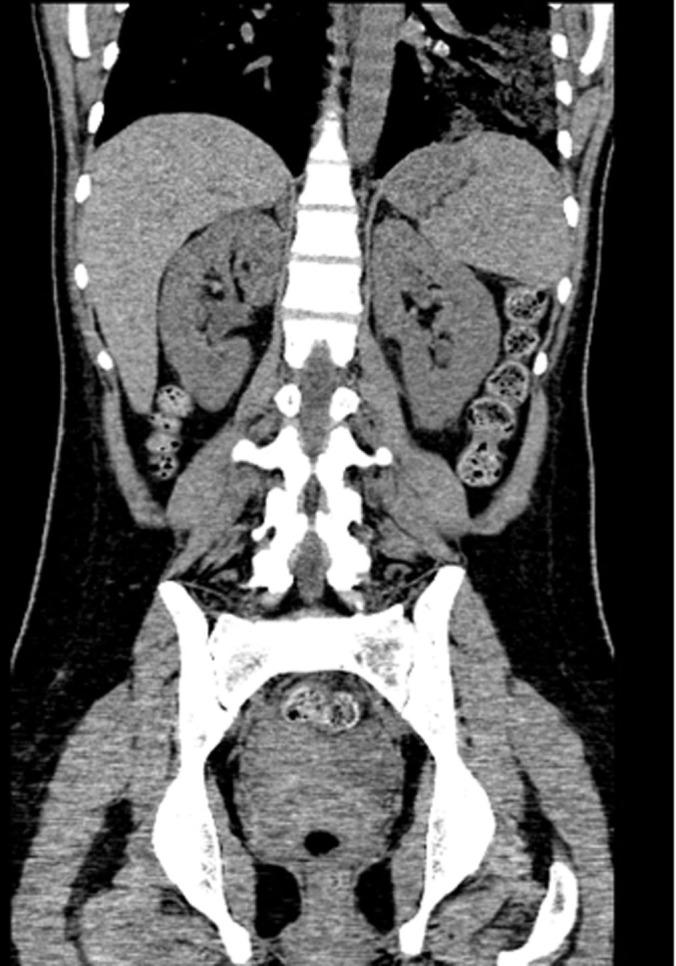

Emphysematous gastritis with portal venous air is a rare condition usually caused by gas forming organisms. This may be secondary to local spread of an infection through the mucosa or rarely hematogenous dissemination from a distant focus. We present a young diabetic woman with uncontrolled diabetes mellitus who was admitted with sepsis and severe abdominal symptoms. Investigation revealed emphysematous pyelonephritis due to E. coli infection associated with emphysematous gastritis and air in the portal tract. She improved with broad spectrum antibiotics, fluid resuscitation and electrolyte and diabetic management. To our knowledge this is the first report showing the association between emphysematous pyelonephritis and gastritis with air in the portal system.